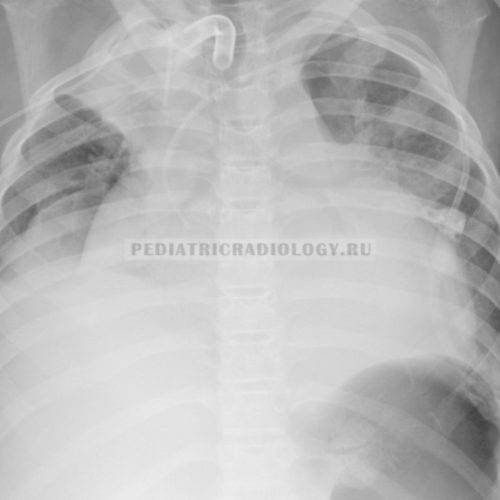

Ателектаз легких у новорожденных

У здоровых новорожденных — преимущественно у недоношенных — ателектаз легкого (частичный) может отмечаться в первые несколько суток жизни. Как правило, такие ателектазы исчезают без какого бы то ни было вмешательства и потому считаются «физиологическими».

Причины возникновения ателектаза у новорожденных разные: это и вдыхание некоторого количества околоплодных вод, и недостаточное содержание так называемого сурфактанта (особого вещества, которое не дает спадаться легочной ткани), и неполное расправление сети легочных сосудов, а также слабый крик при рождении и ослабленное дыхание, в результате чего легкое новорожденного не разворачивается полностью.

Кроме того, ателектазы могут развиться при асфиксии, при пневмониях, при давлении на бронхи увеличенных внутригрудных лимфатических узлов и т.д.

В зависимости от величины и локализации пораженного участка легкого развиваются клинические проявления. Довольно часто за клинической картиной основного заболевания не видно проявлений ателектаза. Кожные покровы у новорожденного могут быть бледны или синюшны; у ребенка — явная одышка. Врач, прослушивающий легкие с помощью фонендоскопа, не слышит дыхания в том месте, которое поражено, или слышит ослабленное дыхание. Перкуторный звук над участком ателектаза укорочен.